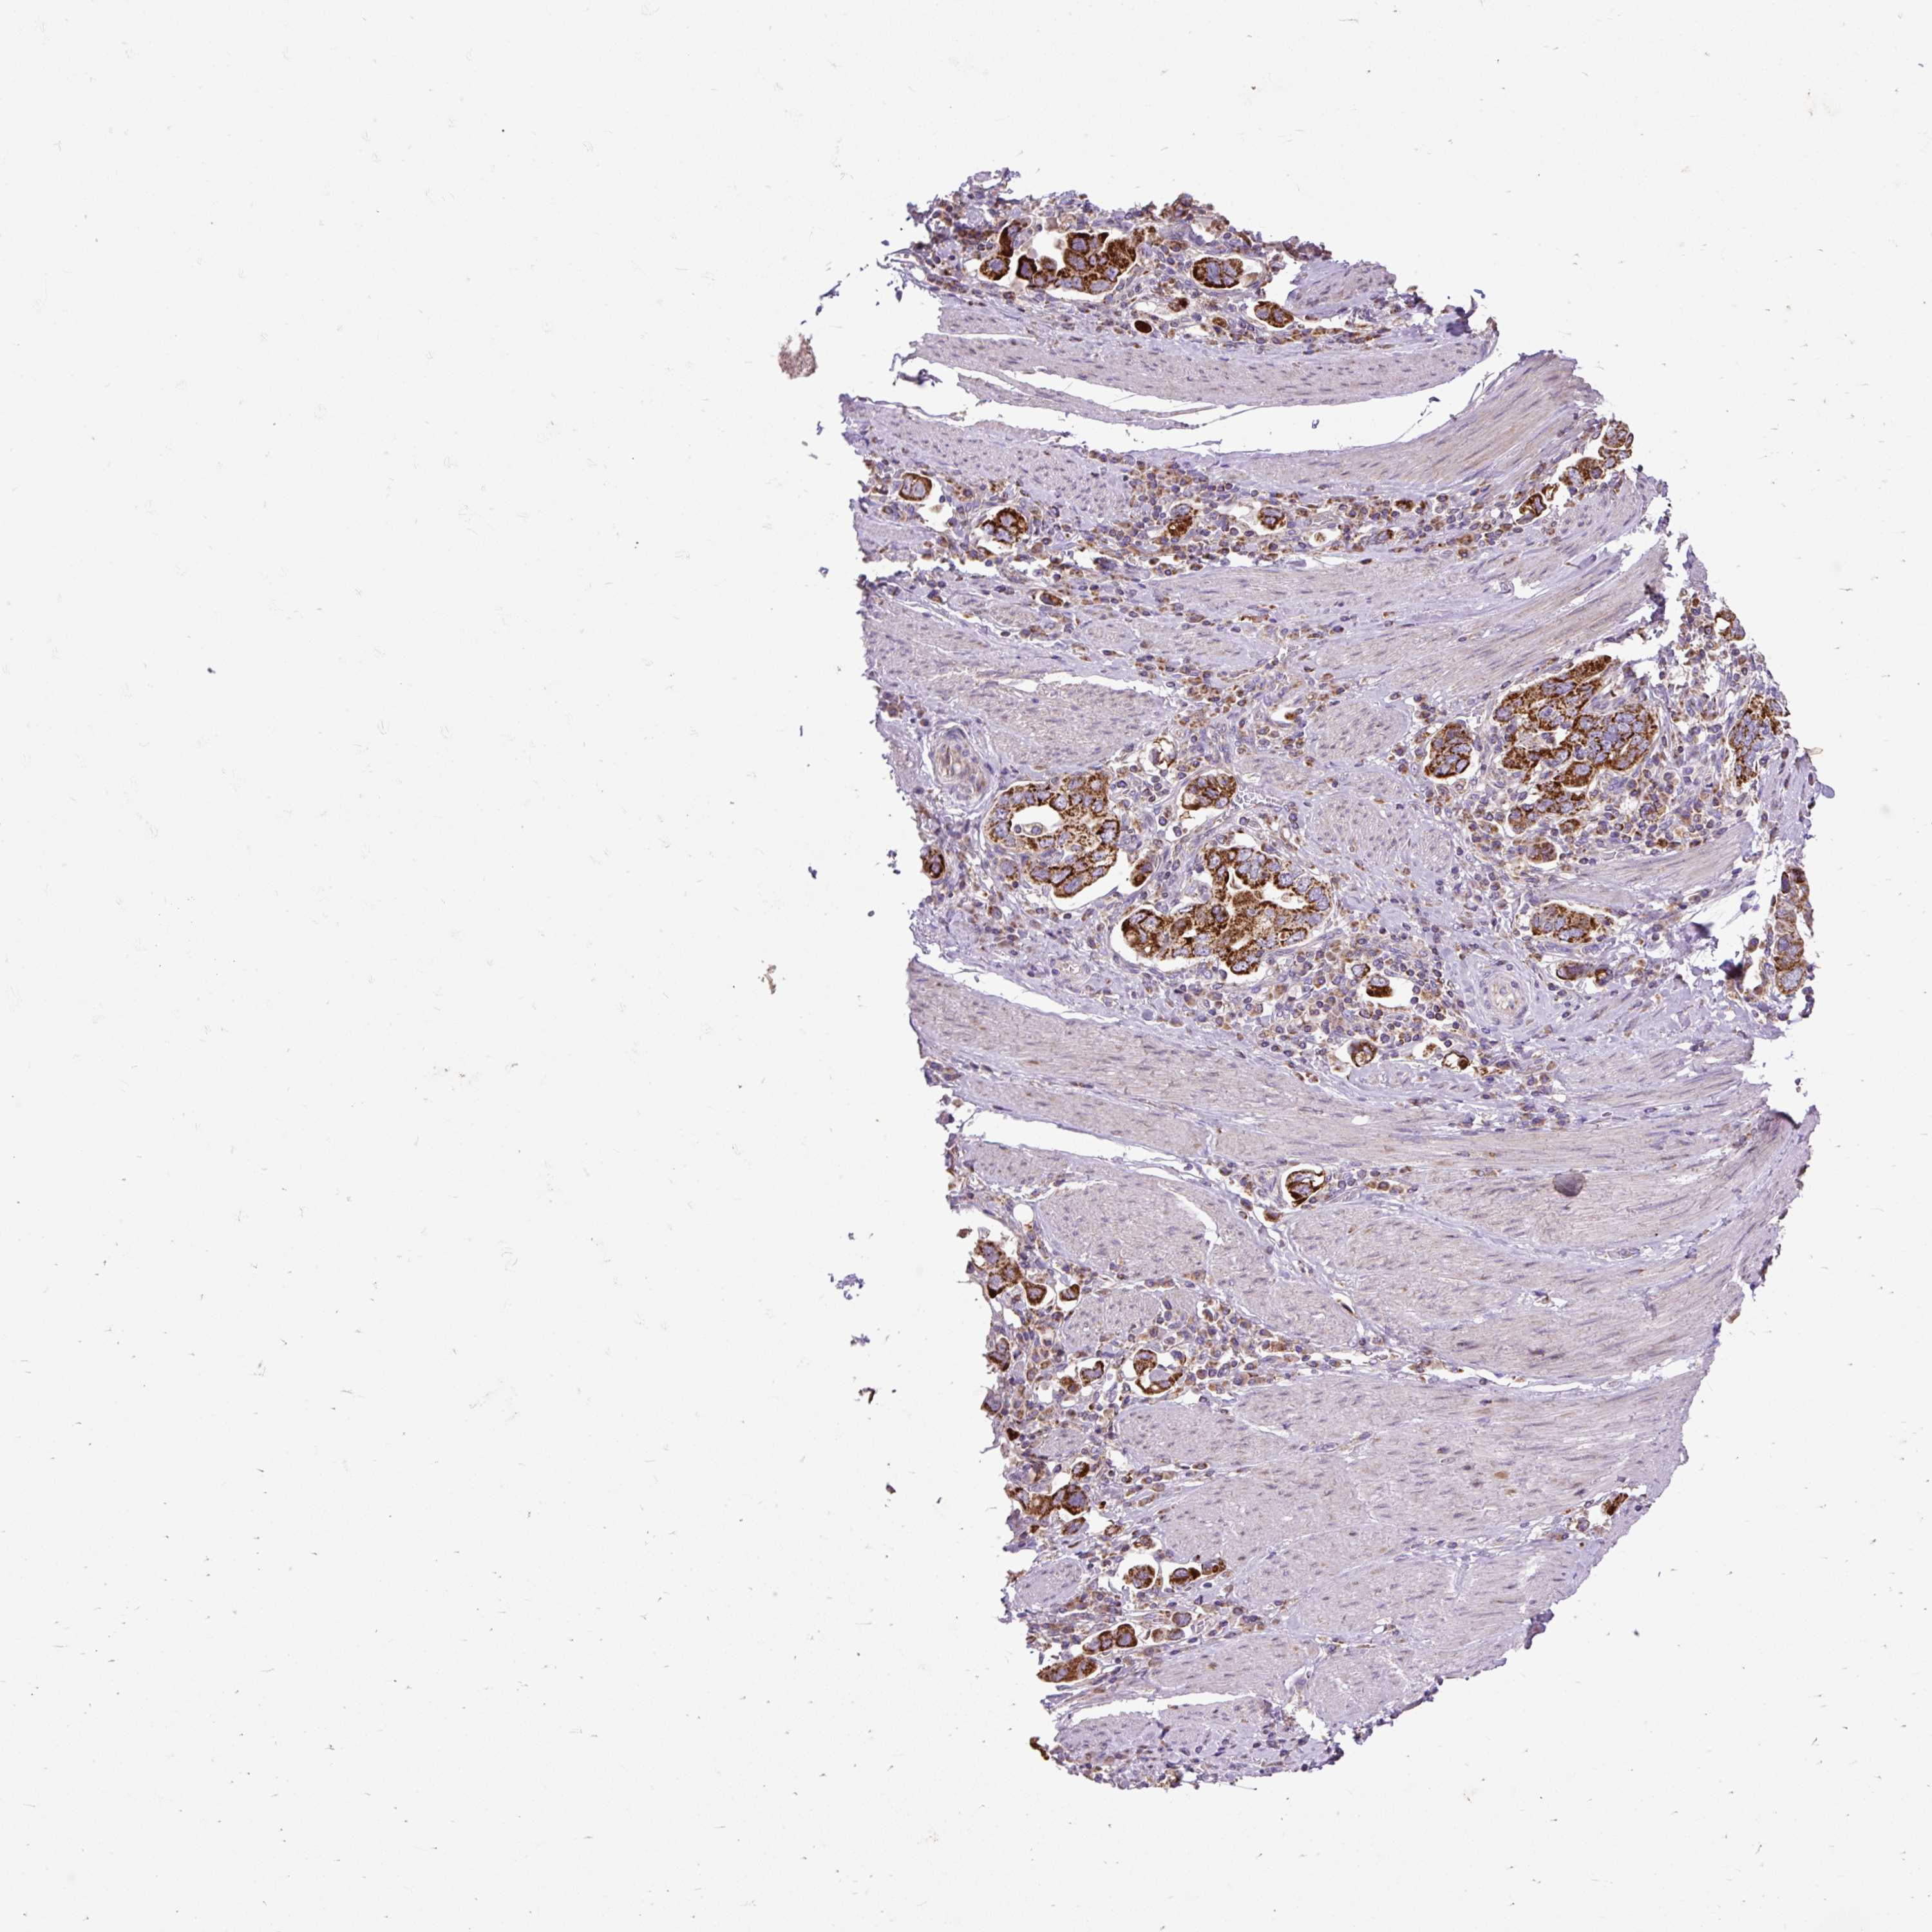

STOMACH CANCER - Protein expressioni

A mouse-over function shows sample information and annotation data. Click on an image to view it in a full screen mode. Samples can be filtered based on level of antibody staining by selecting one or several of the following categories: high, medium, low and not detected. The assay and annotation is described here.

Note that samples used for immunohistochemistry by the Human Protein Atlas do not correspond to samples in the TCGA dataset.

Antibody stainingi

Antibody staining in the annotated cell types in the current human tissue is reported as not detected, low, medium, or high, based on conventional immunohistochemistry profiling in selected tissues. This score is based on the combination of the staining intensity and fraction of stained cells.

Each image is clickable and will lead to virtual microscopy that enables deeper exploration of all samples and also displays staining intensity scores, fraction scores and subcellular localization as well as patient and tissue information for each sample.

Antibody HPA036231

Antibody HPA036232

Staining

High

Medium

Low

Not detected

Intensity

Strong

Moderate

Weak

Negative

Quantity

>75%

75%-25%

<25%

None

Location

Nuclear

Cytoplasmic/membranous

Cytoplasmic/membranous,nuclear

Adenocarcinoma, NOS